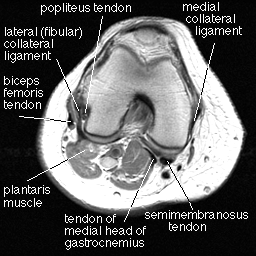

Now, we just need to discuss a few more muscles to collect the whole set. First, look at the plantaris muscle in the image below. This is not a major muscle in humans or other primates, but is large in other mammals. It lies just under the lateral head of the gastrocnemius, and it helps the gastrocnemius flex the ankle and the knee.

The popliteus is a short, flat muscle that helps to build part of the floor of the popliteal fossa. Its main significance lies not in its muscular action (medial rotation of the knee) but in its sometimes bewildering appearance on knee arthrography. Occasionally, it comes in handy in patients with tumors of the proximal tibia, forming a barrier between tumor and the popliteal neurovascular bundle.

The gastrocnemius muscle is a powerful flexor of the ankle and knee. It originates in two heads arising just above the medial and lateral femoral condyles. Distally, these two heads unite with a broad aponeurosis that extends distally to become the Achilles tendon. The lateral head of the gastrocnemius may contain a small sesamoid bone or cartilage called the fabella (Latin for little bean) in about 29 % of the population. It is ossified in about 10 - 12 % of the population, and should not be mistaken for an intraarticular body.

The semimembranosus originates at the ischial tuberosity and runs down the back of the thigh to attach on a horizontal groove on the posterior surface of the medial condyle of the tibia. It extends the thigh and flexes the knee.

A small bursa lies between the semimembranosus tendon and the tendon of the medial head of the gastrocnemius. This bursa may communicate with the knee joint space. On MR, it appears as a triangular or star-shaped area of intermediate intensity between these tendons. The gap between these tendons is a potential weak spot, and fluid may herniate between them, forming a popliteal cyst (Bakers cyst). A joint effusion is almost always seen with a popliteal cyst.